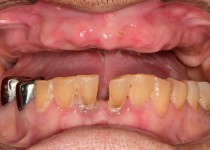

만 52세 전악 상악, 하악 전체 임플란트…

만 56세 상 하악 임플란트 증례